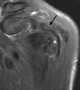

Voluntary subluxation of the shoulder